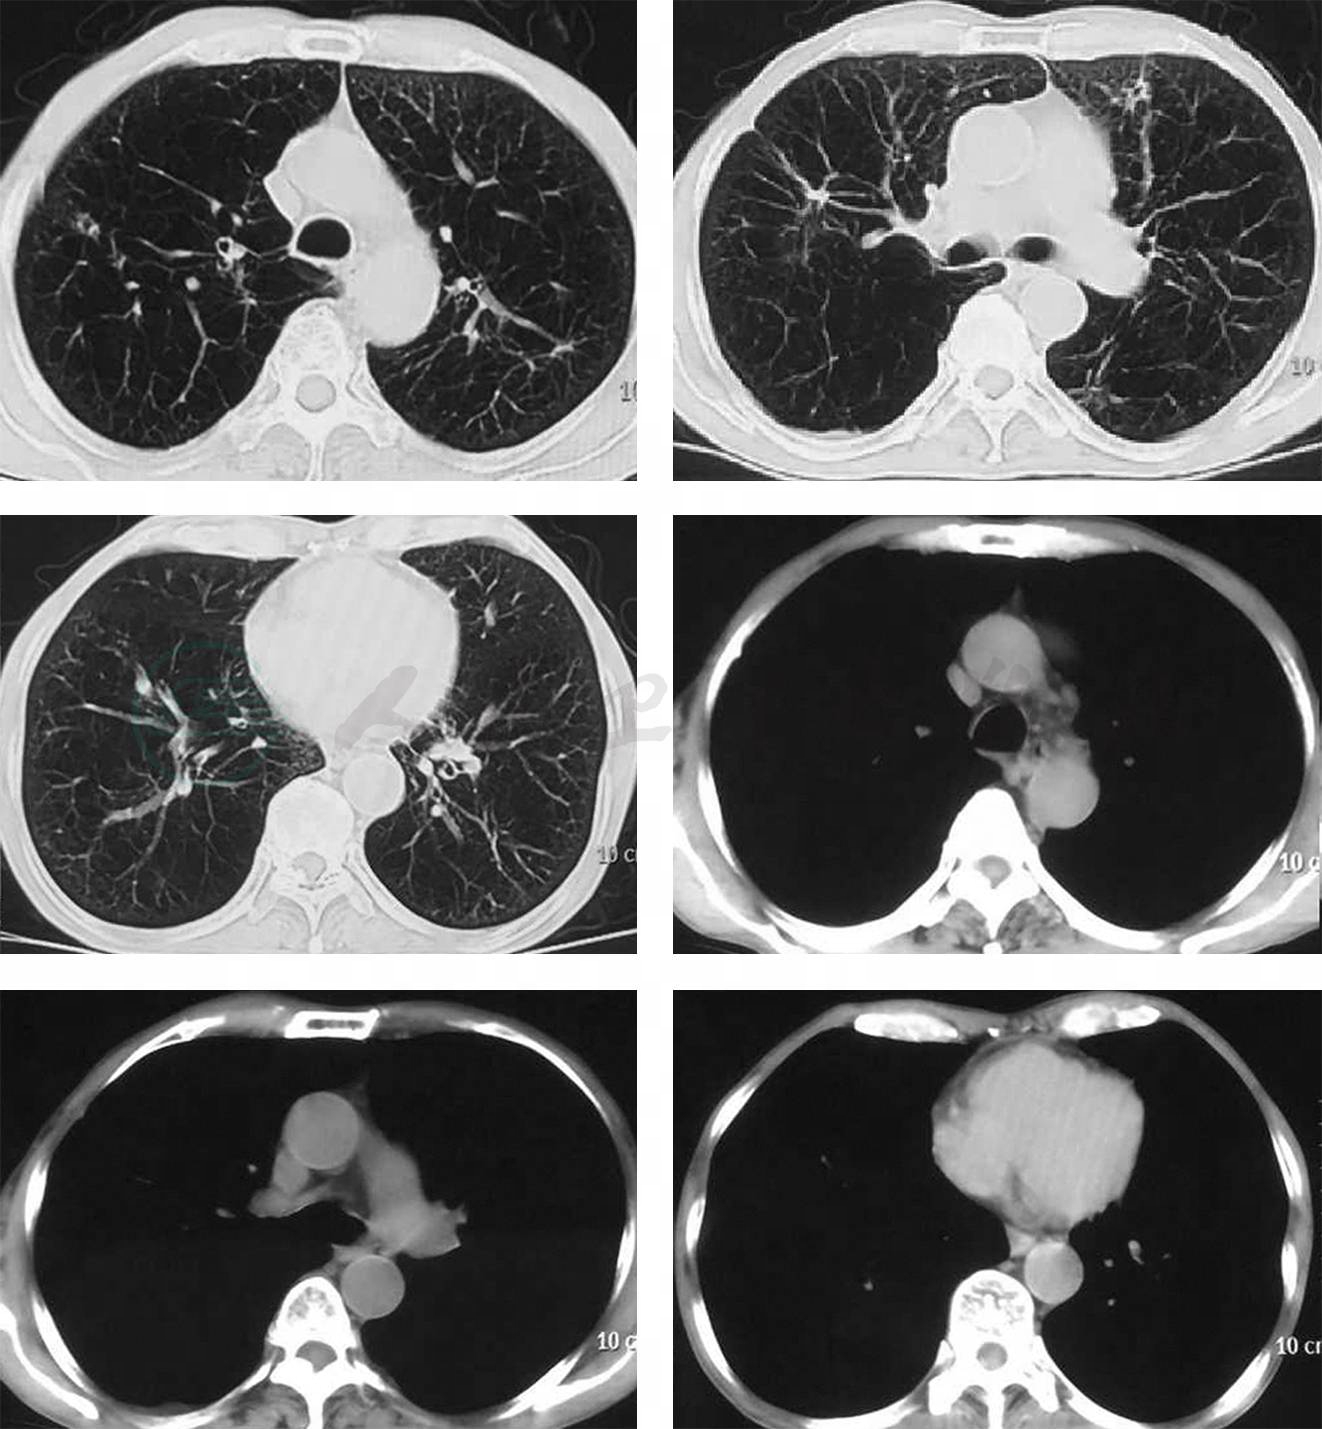

10.入院后病情变化 入院后患者右侧胸痛、气促较前加重,咳金黄色水样痰,持续发热,呼吸衰竭迅速加重,改气管插管+有创呼吸机辅助通气;感染指标迅速升高:血常规示WBC 19×109/L,中性粒细胞百分比88.4%;PCT 5.27ng/ml;CRP 167mg/L;ESR 27mm/h;影像学快速进展(图2);肝功能损害进一步加重(表1);抗感染治疗方案由哌拉西林他唑巴坦升级为头孢噻利+利奈唑胺。俯卧位引流后,患者气管导管引流出大量稀薄金黄色液体,20min内引流出约250ml(图5-3);床旁支气管镜:右下叶较多黄色稀薄分泌物;支气管分泌物革兰氏染色(多次)可见革兰氏阳性球菌和革兰氏阴性杆菌;支气管分泌物、细菌培养、抗酸染色、真菌培养均多次阴性。

图2 肺部影像学(2017年7月11日~15日)